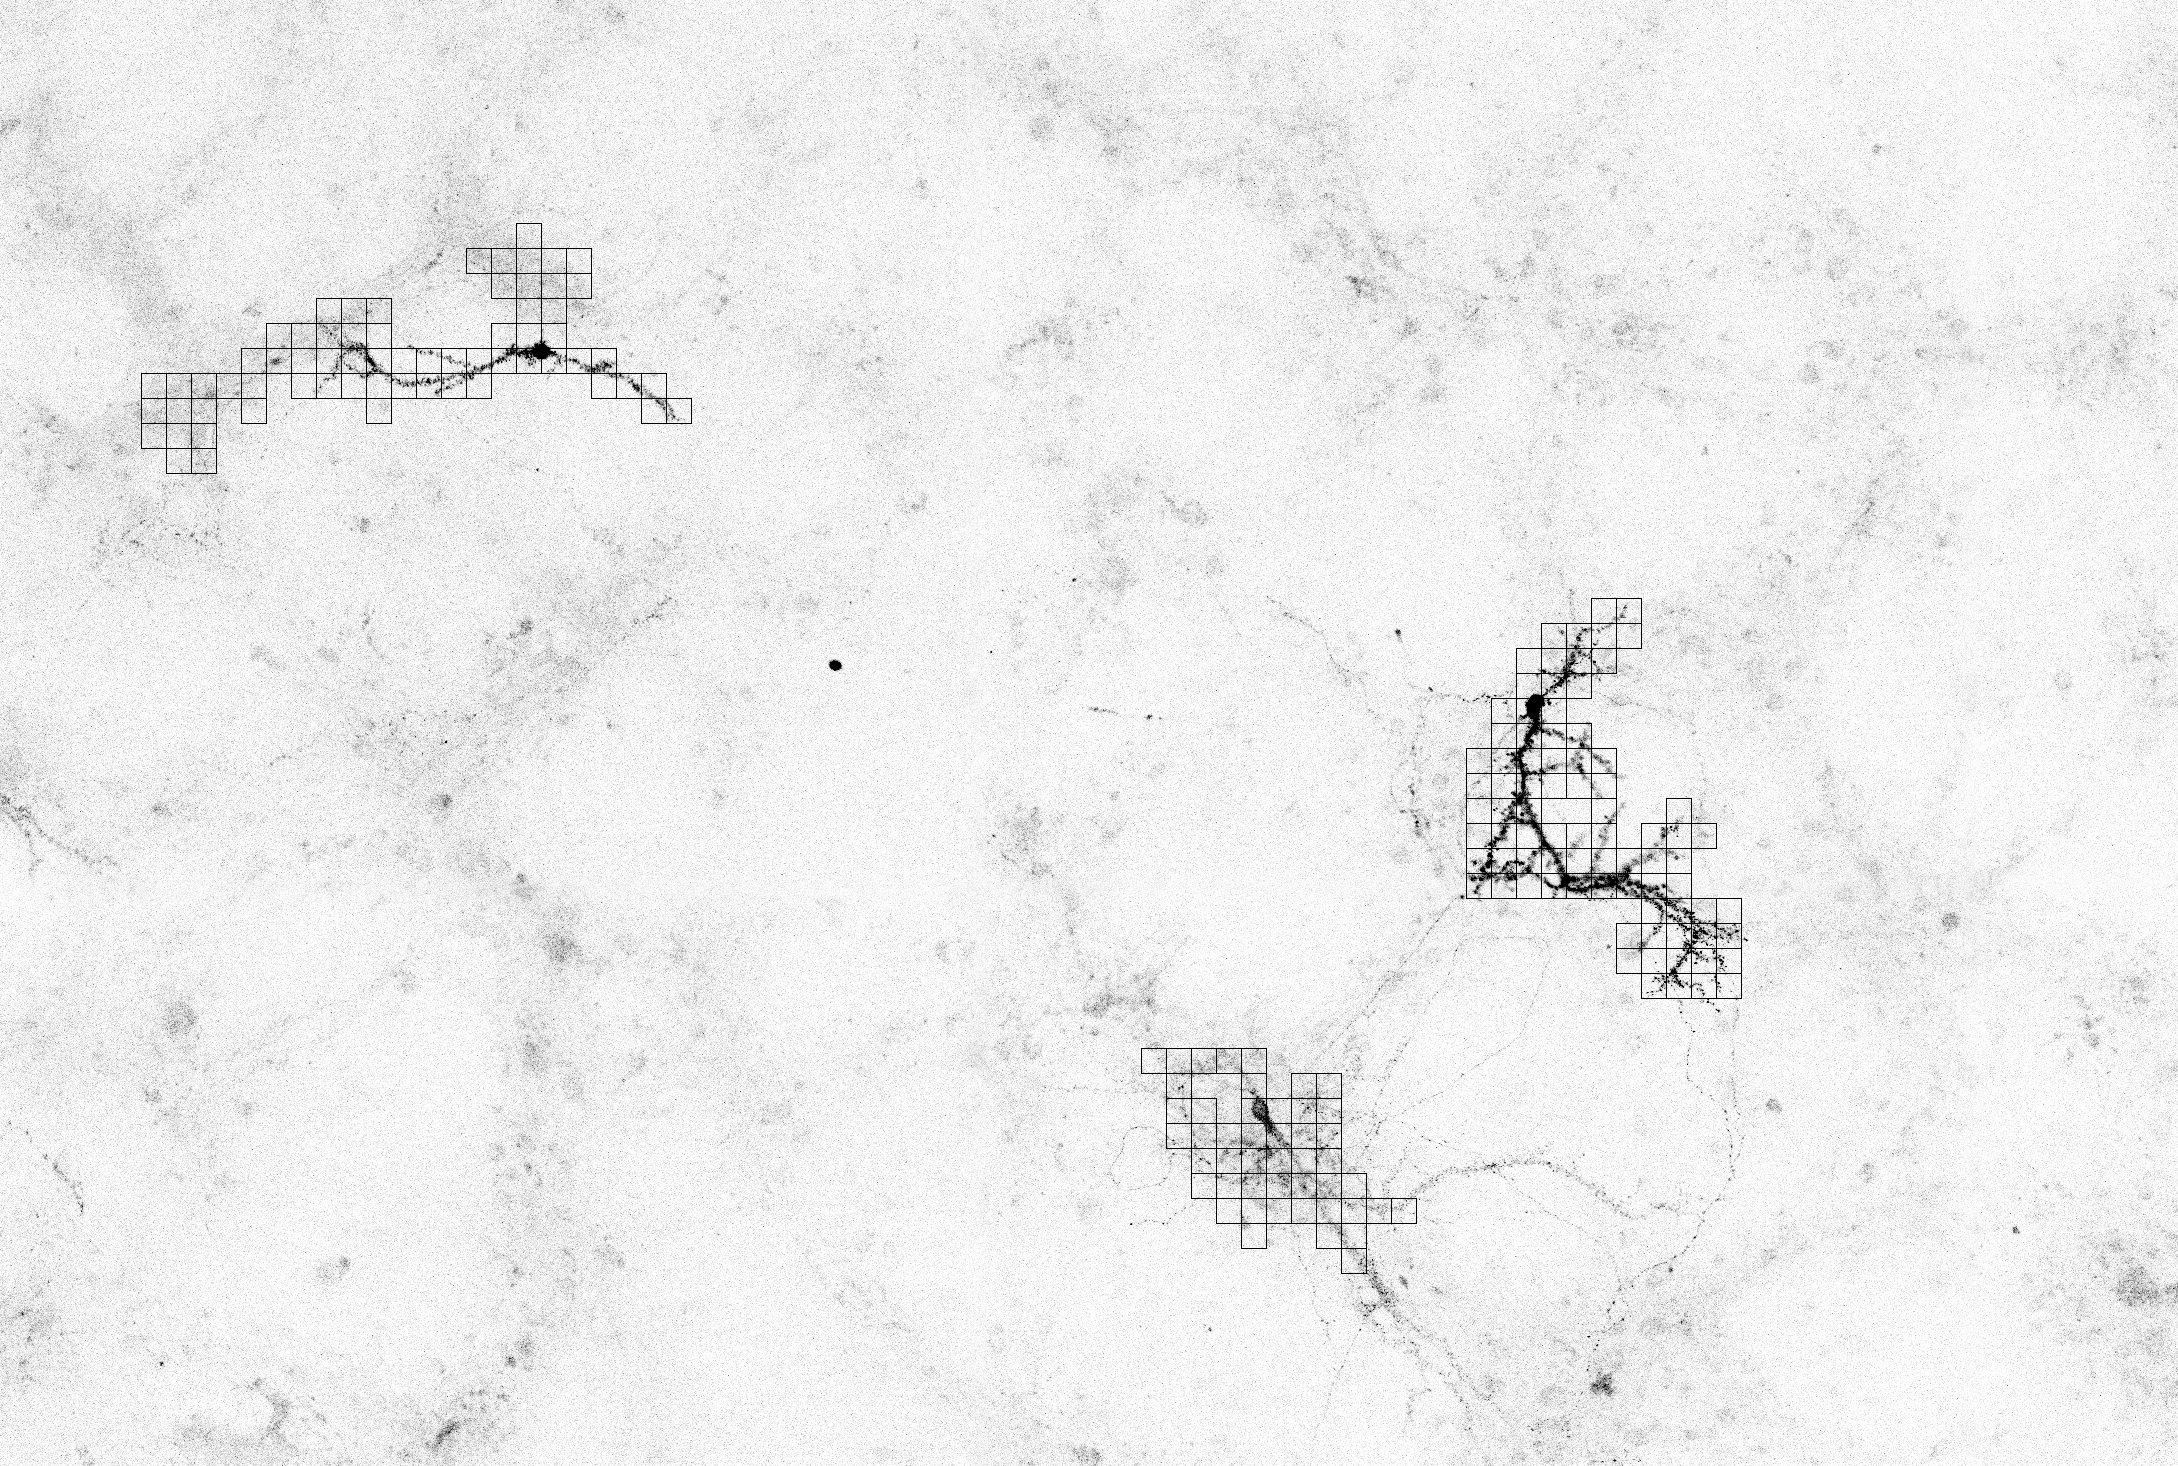

Otro problema considerado consiste en contar el número total de neuronas que aparecen en una imagen de cultivo (véase la figura 2). Para ello hay que localizar los núcleos de neuronas que aparecen en la imagen y diferenciarlos de otros elementos (como astrocitos, células que no son neuronas). Este recuento es necesario para el estudio de la muerte neuronal que se produce, por ejemplo, al sufrir un ictus. En este estudio se compara el número de núcleos disponibles antes y después de la aplicación de una sustancia a la muestra. Las imágenes consideradas en este problema tienen un tamaño de 16193×10279161931027916193\times 10279 píxeles, lo que en este caso equivale a 3676×2333367623333676\times 2333 micras, y se obtienen como un mosaico de 8×5858\times 5 imágenes de tamaño 2048×2048204820482048\times 2048 píxeles (con un solapamiento del 2%percent22\leavevmode\,\%{}).

Refer to caption

Figura 2: Estudio de la muerte neuronal

Como un problema intermedio para el recuento y clasificación de espinas, se ha considerado también el problema de localizar las distintas neuronas que aparecen dentro de una imagen de cultivo. Las imágenes a estudiar en este problema tienen tamaño 12107×917412107917412107\times 9174 píxeles o 9172×6950917269509172\times 6950 micras y se obtienen como un mosaico de 12×912912\times 9 imágenes de 1024×1024102410241024\times 1024 píxeles. Este paso se utilizará como pieza necesaria para el software de recuento y clasificación de espinas; una vez que se tiene la localización de cada neurona, se debería captar otra imagen con una resolución mayor sobre las coordenadas correspondientes y a partir de la nueva foto realizar el cálculo y la clasificación de espinas deseada. En la figura 4, que representa un pequeño fragmento de las imágenes tratadas, pueden observarse tres neuronas.

Figura 4: Imagen con varias neuronas

Por último, el plugin LocationJ, que se encuentra actualmente en fase de desarrollo, permitirá localizar las diferentes neuronas presentes en una imagen de mosaico. Para ello se parte de los puntos de la imagen con mayor intensidad (candidatos a estar en el núcleo de alguna neurona), y se realiza una búsqueda de caminos alrededor de ellos para localizar las diferentes dendritas. Como ya se ha explicado anteriormente, para solucionar el problema de la continuidad, se permiten saltos de 2 o 3 píxeles. El programa muestra una serie de cuadrados indicando el área ocupada por la neurona, como se puede observar en la figura 11. Este plugin será utilizado como pieza intermedia en el programa para el recuento y clasificación de las espinas (uno de los problemas planteados por el grupo de biólogos PSE, que todavía no ha sido tratado).

Figura 11: Resultado de LocationJ